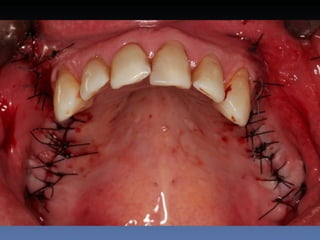

Maria Gomes Moraes

Idade – 53 anos

Sexo – Feminino

Raça – Caucasiana

ASA – II

Data- 23-04-2012

Diagnóstico: Atrofia severa

da pré-maxila.

Plano de tratamento: Aumento de volume horizontal

com blocos ósseos autógenos “onlay” provenientes do

Ramus da Mandíbula.

sutura nylon 4-0

Pós-operatório -5 dias